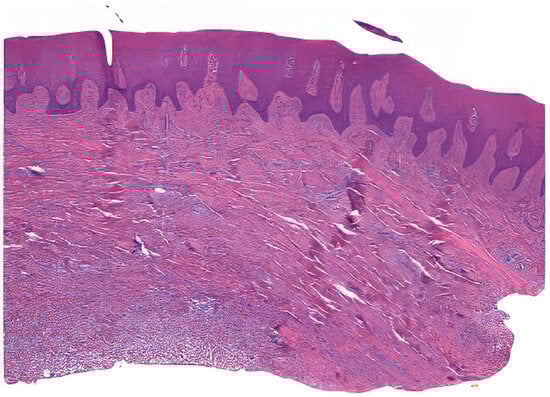

Tissue samples were collected from excess epithelial–connective graft material, which underwent shaping and finishing procedures during surgery. A total of 50 samples from 25 patients were fixed in Karnovsky’s solution (2% paraformaldehyde, 2.5% glutaraldehyde in 0.1 M sodium cacodylate buffer) for 6 h at 4 °C, followed by washing in 0.1 M cacodylate buffer with added sucrose. After fixation in Karnovsky’s solution, the tissue samples were washed in 0.1 M cacodylate buffer with added sucrose to remove excess fixative. The dehydration process involved immersing the samples in increasing concentrations of ethanol (70%, 80%, 90%, 95%, and 100%), followed by clearing in xylene. The cleared samples were then infiltrated with paraffin at 60 °C under vacuum conditions to ensure thorough embedding. Serial sections of the embedded tissue blocks were cut at 4–5 μm thickness using a rotary microtome Leica SM 2400 microtome (Leica Biosystems, Nußloch, Germany). The sections were mounted on glass slides and dried at 37 °C overnight. Hematoxylin and eosin staining was performed (Figure 2) [23].

The stained sections were observed under a Nikon Eclipse 600 (Minato, Tokyo, Giappone) microscope with a Nikon DS-U1 digital sight camera. Two blinded expert operators (AZ and MR) performed the histological and histomorphometric analyses. NIS-Elements software 4.5 version facilitated measurements at low magnification (20×), focusing on parameters such as epithelial height, total graft height, and perimeter (Table 1).

Figure 2. Example of a prepared sample.